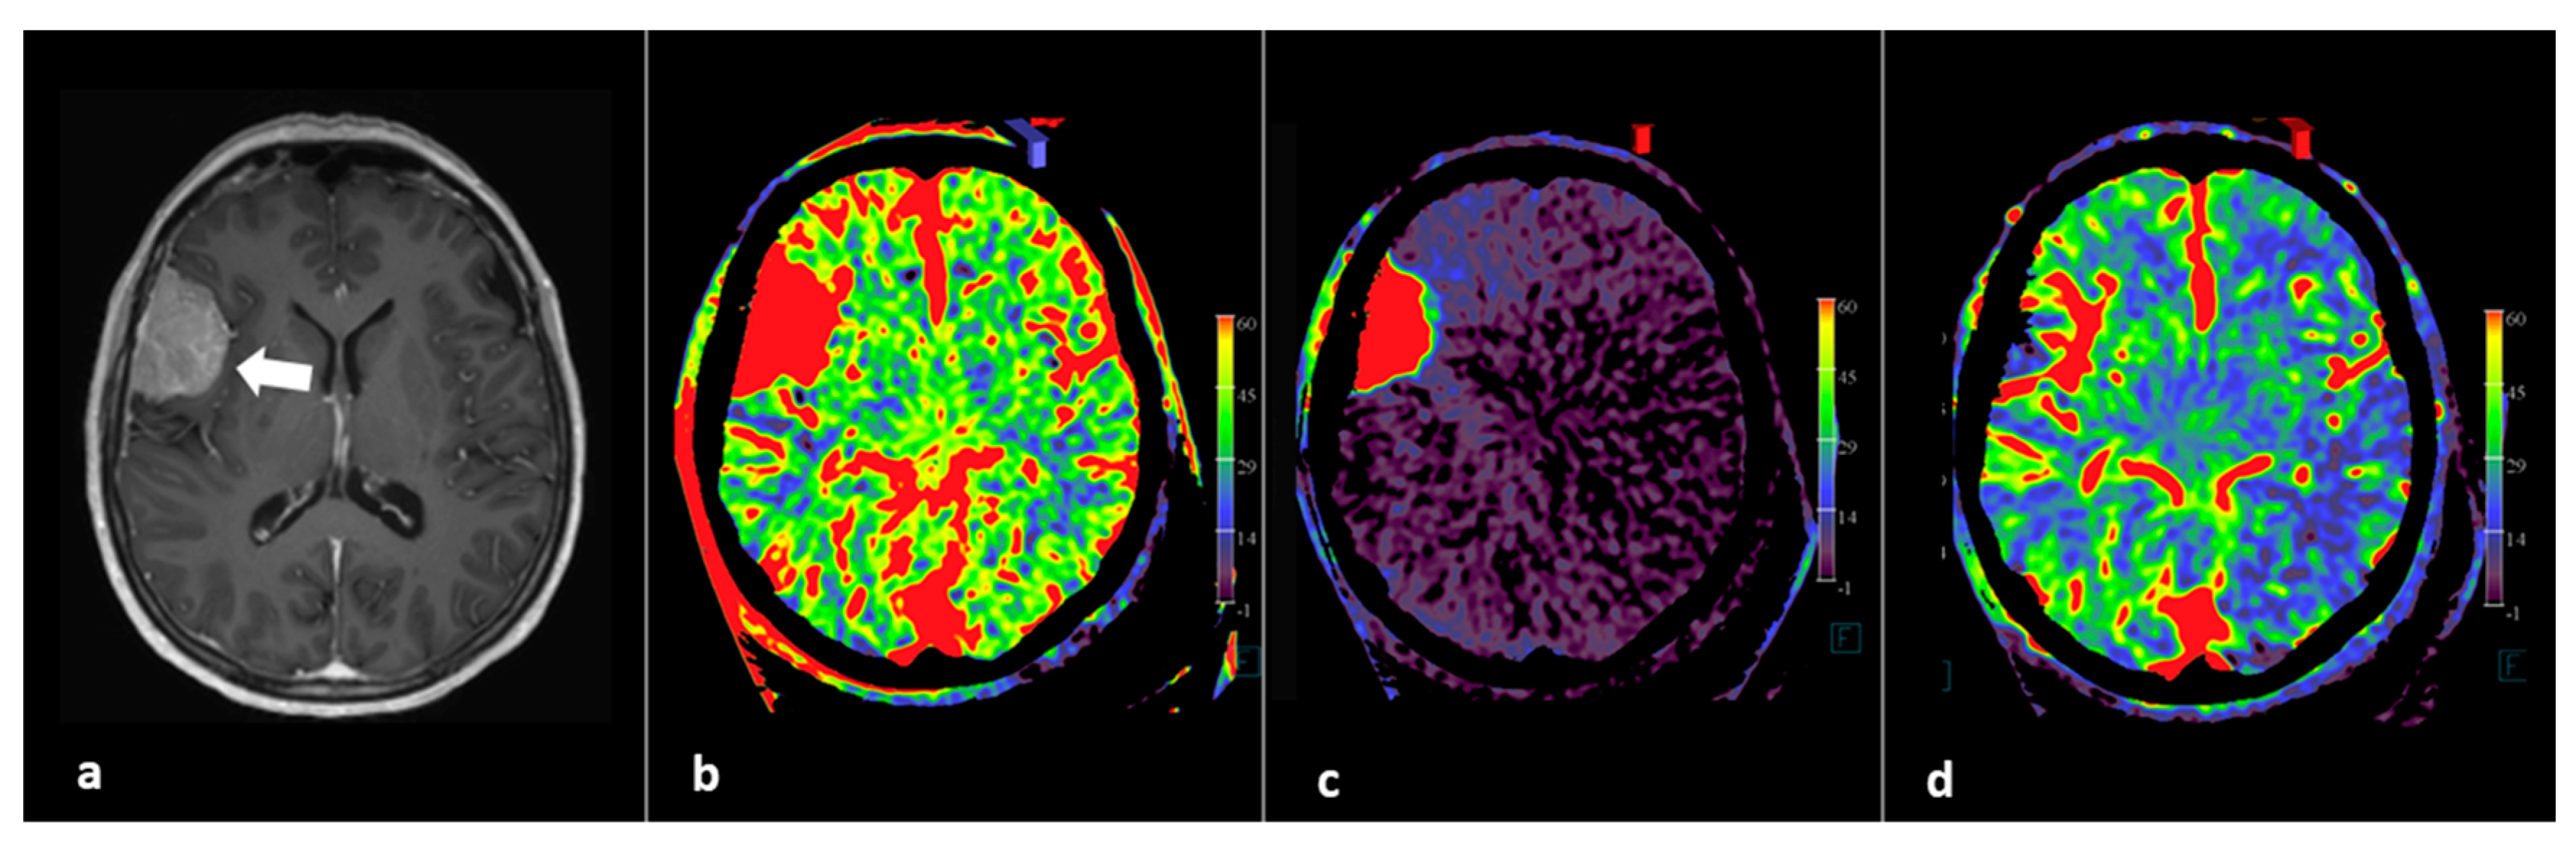

In addition to whole brain neuro PBV imaging, selective contrast injection PBV imaging into tumor feeder vessels can be used to determine more precisely the potential benefit of the intended embolization [37]. Based on the FD CT imaging, the interventional neuroradiologist can immediately decide in the angiography suite, in agreement with the neurosurgeon, whether or not to perform a subsequent embolization procedure and, if applicable, select feeding arteries for embolization. FD CT PBV imaging pre- and post-tumor embolization scanning is demonstrated in Figure 3.

Figure 3.

FD CT PBV imaging in a patient referred for pre-operative tumor embolization. (a) Axial T1-WI image shows right-sided perisylvic meningioma (arrow). (b) Pre embolization axial PBV MIP reformation after aortic root contrast demonstrating whole brain PBV imaging. (c) Pre embolization axial PBV MIP reformation with right external carotid artery (ECA) contrast injection demonstrates dominant dural vascular tumor supply. (d) Post embolization whole brain PBV axial MIP reformation illustrates successful tumor embolization.

Summarizing, FD CT imaging allows exact volume PBV mapping by selective tumor and whole brain contrast injection. However, the exact value of qualitative or regional FD CT PBV measurements pre- and post-tumor embolization has not yet been decided and should be the subject of further research.